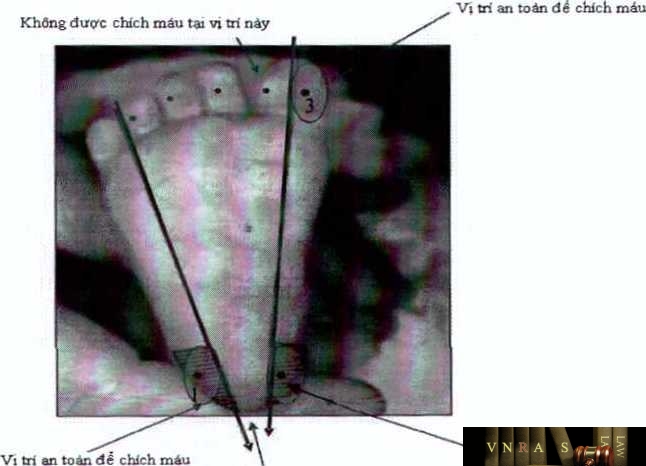

Bước 2: Xác định vị trí lấy

: Tùy thuộc vào cân nặng của trẻ, lựa chọn vị trí lấy máu cho phù hợp (xem hình

1).

- Trẻ nặng < 5kg (từ 1-4 tháng tuổi): chích vào gót chân (vị trí 1 hoặc 2 hình 1)

- Trẻ từ nặng 5kg-10kg (khoảng 4-10 tháng tuổi): chích vào ngón chân cái (vị trí số

- hình 1)

- Trẻ nặng >10kg (khoảng 10 tháng tuồi trở lên): chích vào ngón tay (chích vào cạnh bên của ngón tay áp út)

Lưu ý: Không chích vào phía sau gót chân, vào gần hay phía bên của ngón chân

Hình 1: Vị trí lấy máu ở gót chân hoặc ngón chân cái